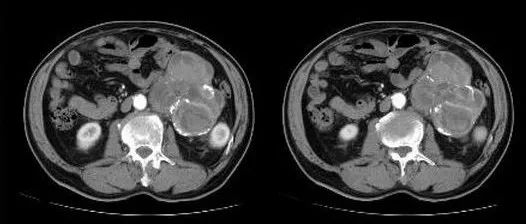

医学影像 yxyx-app 医学影像APP,打造伴随医生快速成长的影像学习社区。与影像园(Xctmr.com)一起提供最全面的影像案例库、基础(解剖、病理、影像诊断)知识、影像技术及考题等,为医生提供最佳的医学影像参考。【所属科室】普外科【基本资料】患者,男,61岁【主诉】腹部外伤一天【影像图片】【讨论问题】如何诊断?【医学影像APP用户讨论】评论:左肾前方巨大肿块,边缘不规则,可见分叶,内部密度欠均匀,有结节状、线状、环形钙化及囊性密度减低区,病灶与胰腺体部关系较密切,左侧肾静脉显示不清,左肾腹部肠管受推压向前移位,左肾受压改变。增强扫描病变可见不均匀异常对比强化。诊断:1.神经源性肿瘤,副节瘤可能大;2. 无功能嗜铬细胞瘤。...